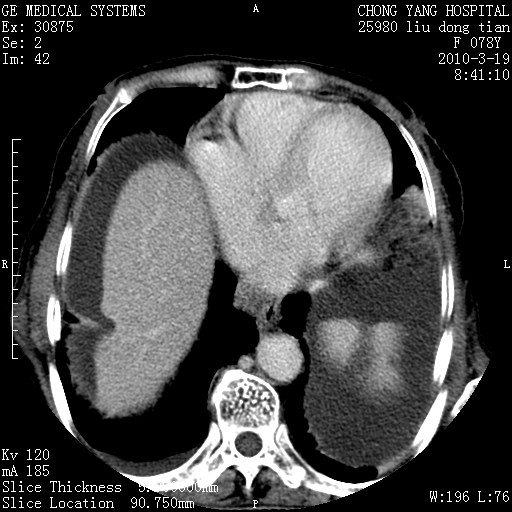

标题: CT25199:F 78Y 腹胀半年 消瘦乏力 [打印本页]

胆囊壁增厚并明显强化,胆囊癌伴多发转移瘤可能性大,淋巴瘤不除外,右肾囊肿,胸腹水.

考虑nhl,肝、脾、腹膜腔及腹膜后多发淋巴结受侵,腹水,右肾囊肿,慢性胆囊炎,右侧少量胸腔积液。

胆囊有软组织影有强化,支持胆囊癌,肝脾、腹膜后淋巴结转移。

nhl的淋巴结多围绕主动脉,而且主动脉会移位,所以不考虑nhl。

分开来讲:肝左叶、尾叶病灶有不均强化像肝癌;

脾脏病灶无强化,像多发囊肿或淋巴管瘤,不除外淋巴瘤(低强化);

胆囊增生性病变:胆囊癌,腺肌增生症,慢性胆囊炎;

肝门、胰腺头、腹膜后多个团块: 淋巴瘤,转移;

腔静脉肝内段细小有无布加可能?

一元论最好了 淋巴瘤所致改变; 胆囊癌转移不像,胆囊周围肝组织清晰,肝癌淋巴结转移?三元论都不止。

最后报的胰头癌多发转移,脾脏单独考虑囊肿或淋巴管瘤。